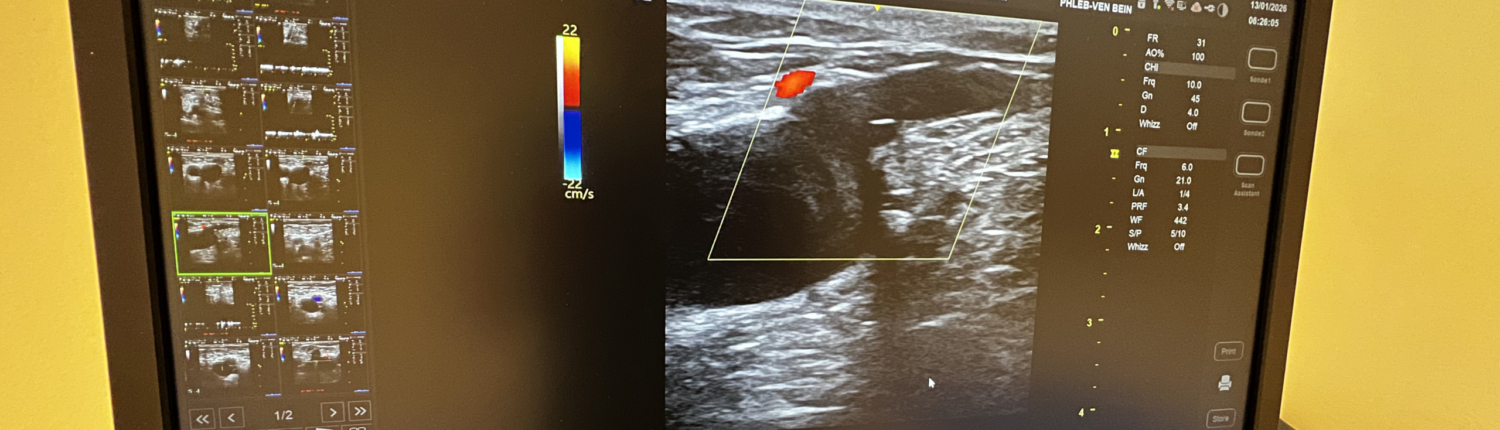

Ein zentraler Baustein unserer Diagnostik ist die Duplex-Ultraschall-Untersuchung. Sie erlaubt eine dynamische Beurteilung „in Echtzeit“ – schmerzarm, ohne Strahlenbelastung und mit hoher Aussagekraft. In der Gefäßchirurgie können damit Durchblutung, Engstellen und Strömungsverhältnisse beurteilt werden; in der Phlebologie dient der Duplex zur Refluxanalyse und zum Venen-Mapping, also zur exakten Planung einer passenden Venentherapie. Bei Verdacht auf akute Ereignisse wie Thrombosen oder bei unklaren Schwellungen ermöglicht der Ultraschall zudem eine schnelle, sichere Abklärung.